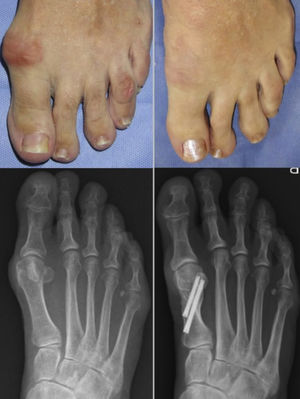

Modified bösch osteotomy surgical techniqueUnder the same conditions as described above, in the Bösch osteotomy using a medial approach, a straight cut is made parallel to the distal joint veneer of the metatarsal at neck level. The wire is advanced in the same way as in the chevron osteotomy in the medullary canal for lateral cephalic displacement.

It is fixed with a screw from proximal towards the head and from medial to lateral, and the K-wire is maintained (Fig. 2). Percutaneous release of the hallux adductor tendon is performed.

Walking in a post-operative shoe with immediate weightbearing is also allowed. Weekly dressings are prescribed and the Kirschner wire is removed in the clinic in the third post-operative week (Figs. 3 and 4).